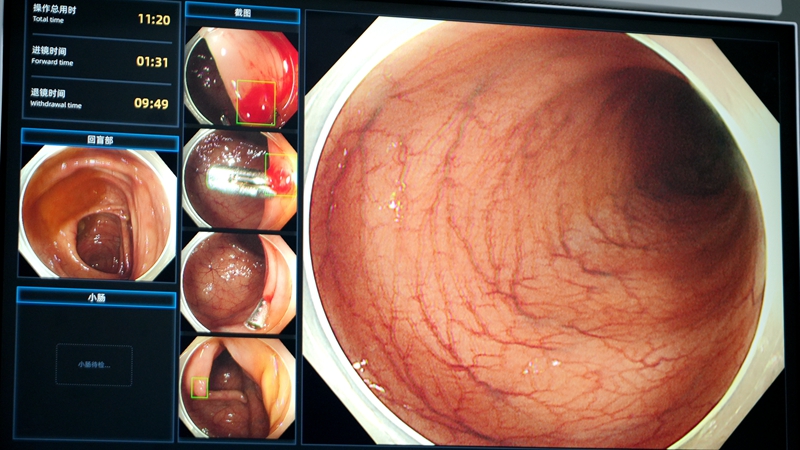

在玉环市人民医院内镜中心,玉环市唯一的“人工智能胃肠镜诊疗系统”也在不断提升胃肠镜诊疗的技术水平。

当医生操作胃肠镜时,AI系统可以通过颜色标记内镜观察到的区域,并对医生的操作时间进行全面监督和提醒,极大提升了内镜检查的完整性。

同时,内镜AI系统通过实时视频分析,可快速识别息肉、溃疡、早癌等病变,并用不同颜色的方框区分标记病灶边界。其中,绿色标记异常区域,黄色标记怀疑早癌区域。

玉环市人民医院医务处处长、消化内科副主任、内镜中心主任姚必瑜说:“在AI的帮助下,操作医生能够更准确地识别和判断病变,有效降低了漏诊率。据统计,2025年第一季度,我们医院的食道早癌和胃早癌的发现率分别提升了25%和40%。”